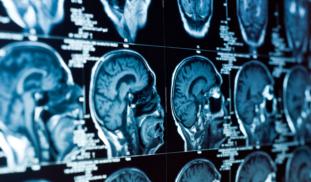

Our 18-week study asks how people living with brain and mind injuries like PTSD or acquired and traumatic brain injury, benefit from simultaneously engaging in multiple recuperative activities. These practices include community service learning, contemporary art interpretation, mindfulness and meditation, and Brazilian Jiu Jitsu. We examine how these activities affect quality of life, brain health, and community integration for people living with brain and mind injuries and their communities.